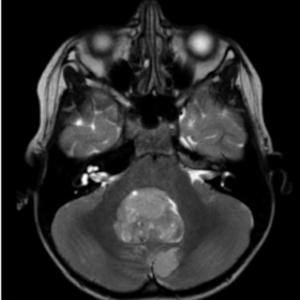

脳梗塞は動脈硬化によって脳血管が詰まった状態、脳出血は血管が破けて出血した状態です。小脳は体のバランスや手足の細かい動きをコントロールする役割があります。その部分に脳梗塞や脳出血が起こるとめまいだけではなく、ろれつが回らない、手足の痺れなどの神経症状がみられることが多いです。

脳腫瘍の初期症状としてめまいやふらつきが現れることがあります。めまいに加えて頭痛や吐き気、歩行時のふらつきや呂律が回らないといった神経症状を伴うことが多いです。

脳の変性とは神経細胞が徐々に機能を失い、壊れていく状態です。高齢の方に多いです。代表的な疾患として脊髄小脳変性症や多系統萎縮症などがあり、MRIで小脳や脳幹の萎縮がみられることがあります。

当院ではめまいの性状、起こり方などの病歴を丁寧に聴取し診察を行い、めまいの種類や分類を可能な限り見極めることを大切にしています。危険なめまい(脳梗塞や脳腫瘍)を除外する目的で必要があればMRI検査も行えます。